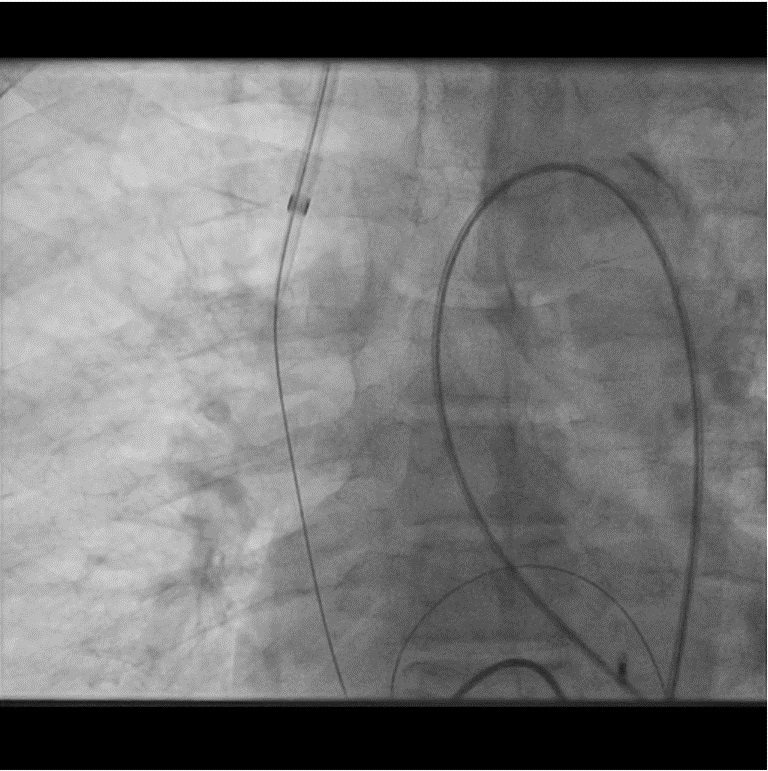

A 65-year-old hypertensive, diabetic male presented with acute anterior wall MI (window 72 hrs) complicated by cardiogenic shock and apical ventricular septal defect (VSD) on echocardiography, showing a significant left-to-right shunt with severe PAH and EF 35%. An intra-aortic balloon pump (IABP) was inserted for hemodynamic stabilization. The procedure was performed via dual access — 6F femoral arterial sheath and 8F internal jugular venous sheath. The left ventricle was cannulated, and the VSD was carefully crossed using a catheter and guidewire, which was advanced into the pulmonary artery. The wire was then snared through the VSD defect to establish an arteriovenous loop, providing stability for device delivery. Over this loop, an Amplatzer 14 mm ASD device was advanced through the 8F sheath and positioned across the apical VSD under echocardiographic and fluoroscopic guidance. After confirming proper alignment and stability, the device was successfully released, achieving complete closure of the shunt. Immediate echocardiography confirmed no residual flow across the septum. The patient was transferred to the CCU for monitoring, with gradual IABP weaning over 4–5 days. Follow-up echocardiography before discharge showed no residual shunt, improved hemodynamics, and stable LV function.